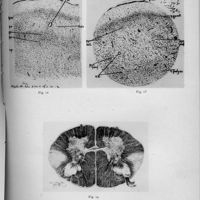

- Contribution anatomo-clinique à l'étude du syndrome de Foerster

- Marinesco, G.

- Dragonesco, S.

- 1929

- [L'] Encéphale (Paris), Vol. 24, pp. 685-99

- Foerster (syndrome de)